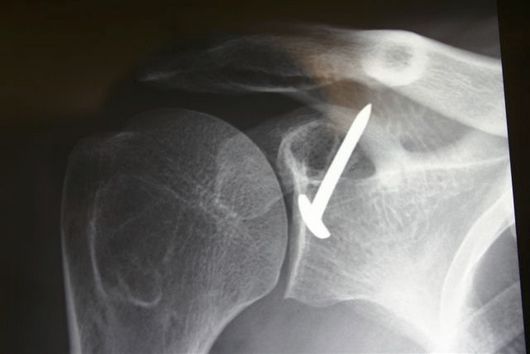

(unpublished data, courtesy of Gilles Walch) At the beginning of the 1950s, Albert Trillat, the head of the orthopedic surgical clinic at the Edouard Herriot Hospital in Lyon (France) and also the promoter of the "no touch technique", reported combination of an anterior labro-ligamentous complex reinsertion when feasible with a reduction of a so-called coraco-glenoid outlet by means of a coracoid osteoclasy and nail fixation (Figures).[14]

Postoperative anteroposterior X-ray of a right Trillat.

Another surgeon, Michel Latarjet, who was mainly active in the field of thoracic surgery, visited Dr. Trillat to learn the aforementioned technique. When Latarjet supposedly tried to reproduce the Trillat procedure, he carried an involuntary complete coracoid osteotomy. Thenceforth, not knowing what to do with the bony fragment, he fixed it to the anterior glenoid through the subscapularis using a screw. From this mishap was born the operation which now bears his name.[12]